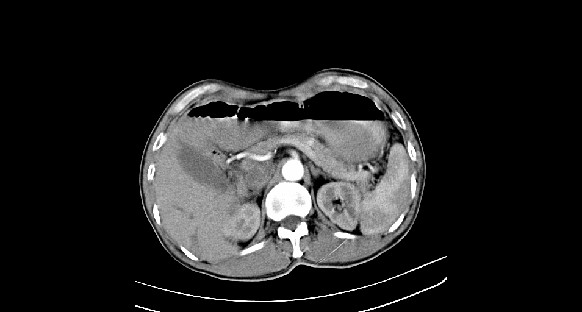

男性,70岁,体检b超发现左肾占位,请各位战友发表一下观点

左肾有两个病灶,且较大的病灶内可见点状钙化灶,增强扫描边缘也是呈渐进性强化,中央部分未见明显强化